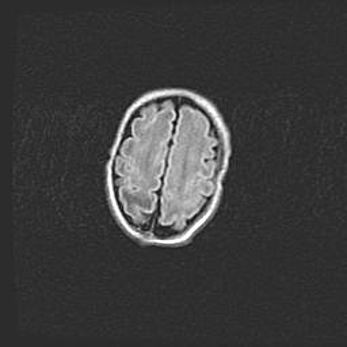

Наружная гидроцефалия с возможной атрофией височных областей.

Возраст: 28 дней

Вес: 3670 г

Пол: мужской

Окружность головы: 38 см

Срок гестации: 40 недель

Гидроцефалия головного мозга у новорожденных – это заболевание, которое характеризуется скоплением избыточного количества спинномозговой жидкости в желудочковой системе головного мозга в результате затруднения её перемещения от места выработки к месту поглощения в кровеносную систему или вследствие нарушения абсорбции. При открытой наружной форме гидроцефалии у новорожденных расширяются и переполняются субарахноидные пространства.

При нормотензивных  формах,  которые,  как  правило,  являются  следствием  перенесенных ишемических  повреждений  паренхимы  мозга,  возможно  сочетание микроцефалии  с нормотензивной гидроцефалией. В основе данных изменений лежит атрофия больших полушарий с преимущественной  локализацией  в  лобно-височных  областях.